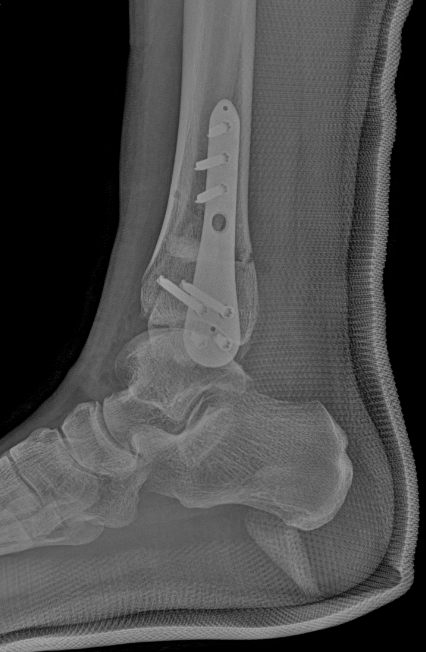

武勇主任团队给他做了3D打印导板辅助下人工全踝关节置换术。

这种手术适合踝关节病严重的患者,通过替换病变的关节结构,能帮着缓解疼痛、恢复关节活动,让老人日常走路更自在些。

术后侧位X线

术后正位X线